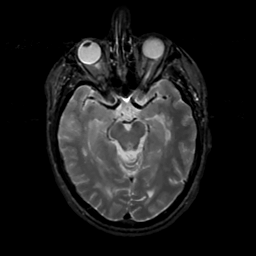

MR Study #16, June 23, 1991 -- Slice #20